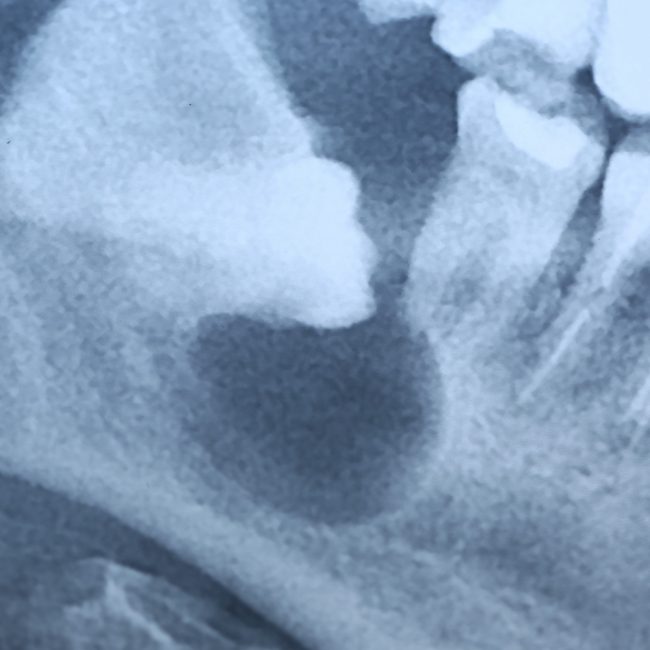

— ортопантомография или, что лучше, конусно-лучевая компьютерная томография. По данным рентгенологического обследования можно определить стадию формирования зуба, направление его движения, отношение к прилежащим структурам, соседним зубам, а также форму и размер образовавшейся под капюшоном полости.

— по данным рентгенодиагностики (КЛКТ или ортопантомограммы) зуб находится в стадии прорезывания (верхушки корней не сформированы), ось прорезывания зуба имеет более-менее правильное направление, его коронковая часть не повреждена кариесом.

— если по данным рентгенологической диагностики причинный зуб имеет сформированную корневую систему, зуб явно уже не прорезывается или, что хуже — упирается коронковой частью в наружную косую линию, соседний зуб или куда-нибудь еще